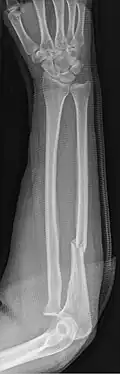

An ulna fracture is a break in the ulna bone, one of the two bones in the forearm.[2] It is often associated with a fracture of the other forearm bone, the radius.[1][3]

An ulna fracture can be a single break as in a so called nightstick fracture, which can be caused by someone being hit on the inside of the forearm often by a stick, notably when they are holding their arm up to protect their head from injury.[2][4] The ulna bone can also break after falling on the forearm or falling on an outstretched arm.[2]

Fractures of the ulna can occur at different levels of the bone: near the wrist, in the middle or near the elbow.[2] The fracture may be confined to the ulna or accompanied with damage to the radius or the wrist or elbow joints.[2]

- Nightstick fracture is a fracture of the middle portion of the ulna without other fractures.[1]

- Distal ulna fractures typically occur along with distal radius fractures.[3]

- Hume fracture - a fracture of the olecranon with an associated anterior dislocation of the radial head.[6]

- Monteggia fracture - a fracture of the near to elbow end of the ulna with the dislocation of the head of the radius at the elbow joint.[2]

- Galeazzi fracture - not a fracture of the ulna but a displaced fracture of the radius accompanied by a dislocation of the ulna at the wrist, where the radius and ulna come together.[2]